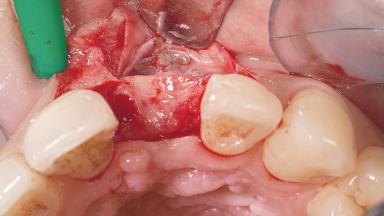

A 30-year-old female patient had lost tooth 21 and was referred to our clinic for consultation and treatment. Due to advanced apical infection, tooth 21 had been extracted two months earlier at another clinic and an acrylic-resin tooth had been bonded to the adjacent teeth. The patient desired implant treatment to avoid any damage to the adjacent natural teeth. While the patient had no history of any systemic disorder, she was a heavy smoker and exhibited medium to advanced periodontitis in the entire jaw. After the initial treatment to achieve a pocket probing depth of less than 4 mm and no bleeding on probing, a decrease in the height of the papillae mesial and distal to the extraction site and overall gingival recession were observed.

Bone Augmentation | Horizontal|Staged |

Augmentation Materials | Autogenous chips|Membrane |